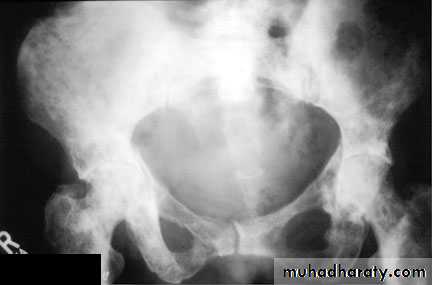

Produce similar changes except:

* Plain film shows evidence of metastasis to the bone especially in the pelvis .* The prostatic urethra shows irregular narrowing and stretching .